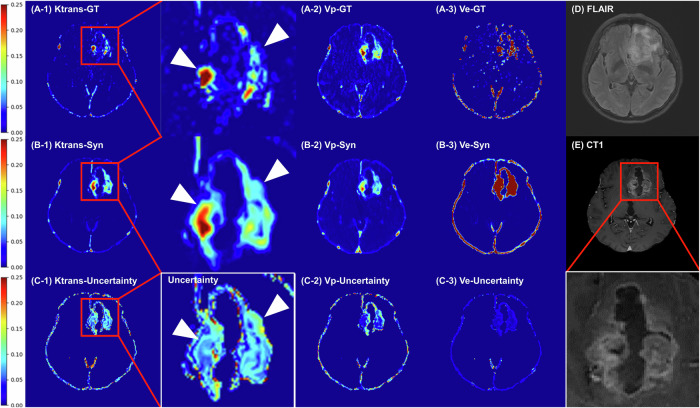

Objectives: To propose and evaluate a novel deep learning model for directly estimating pharmacokinetic (PK) parameter maps and uncertainty estimation from DCE-MRI.

Methods: In this single-center study, patients with adult-type diffuse gliomas who underwent preoperative DCE-MRI from Apr 2010 to Feb 2020 were retrospectively enrolled. A spatiotemporal probabilistic model was used to create synthetic PK maps. Structural Similarity Index Measure (SSIM) to ground truth (GT) maps were calculated. Reliability was evaluated using the intraclass correlation coefficient (ICC) for synthetic and GT PK maps. For clinical validation, Area Under the Receiver Operating Characteristic Curve (AUROC) was obtained for predicting WHO low vs high grade and IDH-wildtype vs mutant.

Results: 329 patients (mean age, 55 ± 15 years, 197 men) were eligible. Synthetic Ktrans, Vp, Ve maps showed high SSIM (0.961, 0.962, 0.890) compared to the GT maps. The ICC of PK maps was significantly higher in synthetic PK maps compared to the conventional approach: 1.00 vs 0.68 (p < 0.001) for Ktrans, 1.00 vs 0.59 (p < 0.001) for Vp, 1.00 vs 0.64 (p < 0.001) for Ve. PK values of enhancing tumor portion obtained from synthetic and GT maps were comparable in AUROC: (1) Ktrans, 0.857 vs 0.842 (p = 0.57); Vp, 0.864 vs 0.835 (p = 0.31); and Ve, 0.835 vs 0.830 (p = 0.88) for mutation prediction. (2) Ktrans, 0.934 vs 0.907 (p = 0.50); Vp, 0.927 vs 0.899 (p = 0.24); and Ve, 0.945 vs 0.910 (p = 0.24) for glioma grading.

Conclusion: Synthetic PK maps generated from DCE-MRI using a spatiotemporal probabilistic deep-learning model showed improved reliability without compromising diagnostic performance in glioma grading.

Key points: Question Can a deep learning model enhance the reliability of dynamic contrast-enhanced MRI (DCE-MRI) for more consistent and clinically acceptable glioma imaging? Findings A spatiotemporal deep learning model outperformed the Tofts model in Ktrans reliability and preserved diagnostic performance for IDH mutation and glioma grade, bypassing arterial input function estimation. Clinical relevance Enhancing DCE-MRI reliability with deep learning improves imaging consistency, supports molecular tumor characterization through reproducible pharmacokinetic maps, and enables personalized treatment planning, which might lead to better clinical outcomes for patients with diffuse gliomas.